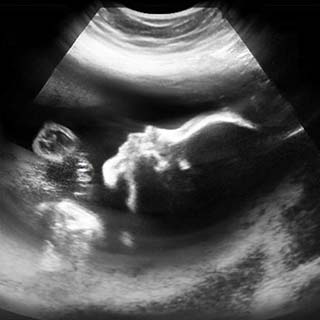

تصویر دو بعدی هفته بیست و هشتم بارداری

در این زمان از بارداری طول جنین ۱۶ اینچ و وزن آن در حدود ۴ پوند است.

ممکن است در تصاویر سونوگرافی دیده شود که جنین شما چاق است. علت آن چربی است که در زیر پوست در حال ساخته شدن است.

در این مرحله از بارداری، چشم ها باز می شوند و ابروها و پلک ها به طور کامل شکل می گیرند و حتی مژه ها هم قابل مشاهده هستند.